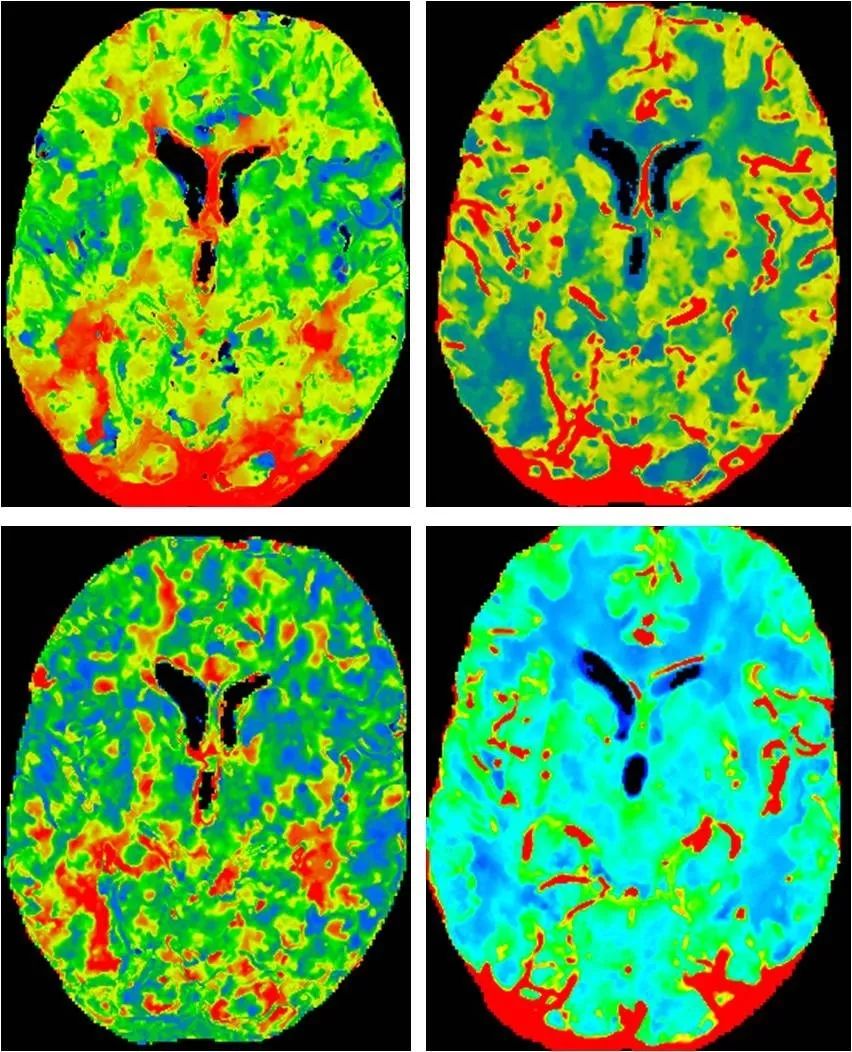

CTP:右大脑中动脉供血区低灌注(图6)。

图6

复查CTP:右侧额颞顶区域灌注较前明显改善(图19)。

图19